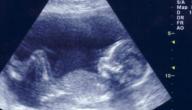

يُعدّ الاستماع إلى نبض الجنين لأوّل مرّة أمرًا في غاية الأهمية؛ ذلك للتأكّد من صحّة الحمل، ويُسمَع صوت هذه النبضات أوّل مرة بعد إتمام ستّة أسابيع من الحمل عن طريق الموجات فوق الصّوتية، إذ يُعدّ الأسبوع السابع من الحمل الوقت الأفضل لتقييم نبضات قلب الجنين، وغالبًا ما يبدو الموعد الأوّل لسماع النبضات بواسطة الموجات فوق الصوتية للبطن في هذا الأسبوع للتأكّد من علامات الحمل الصحي.[٢]

ويجب أن يتراوح معدل دقات قلب الطفل 90-110 نبضة في الدّقيقة ما بين الأسبوعَين السادس والسابع من عمر الحمل، بينما يجب أن يصل معدّل نبضات القلب في الأسبوع التاسع إلى ما بين 140-170 نبضة في الدّقيقة.[٢]